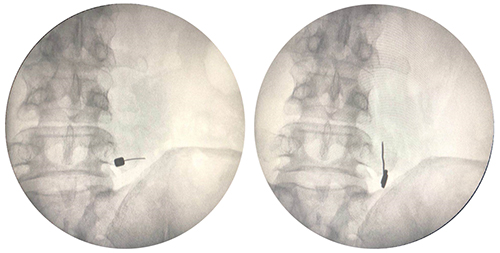

宋文阁教授为张大爷做了右侧L5横突和髂腰韧带处消炎镇痛液和臭氧注射,并在此处进行了小针刀松解。治疗刚结束,张大爷就感到疼痛得到了极大的缓解,翻身和起坐也不会再诱发腰疼。在后续巩固治疗后,张大爷带着满意的笑容出院了。